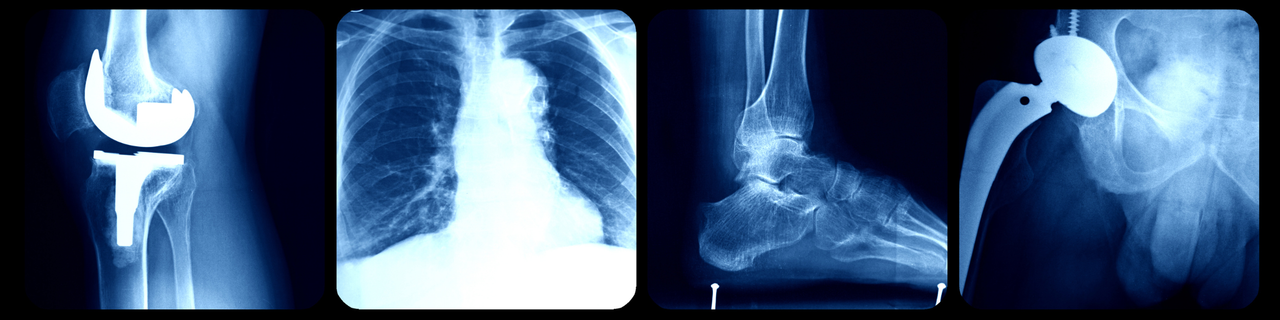

What Can Orthopaedic Surgeons Fix with Surgery?

- Joint Replacement Surgery: Procedures like hip or knee replacement to replace damaged joints with prosthetics.

- Arthroscopy: Minimally invasive surgery using a camera to diagnose and treat joint issues.

- Spinal Surgery: Operations to address conditions like herniated discs or spinal deformities.

- Fracture Repair: Using hardware like plates, screws, or rods to stabilize broken bones.

- Ligament and Tendon Repairs: Reconstructing torn ligaments or tendons, such as ACL repairs.